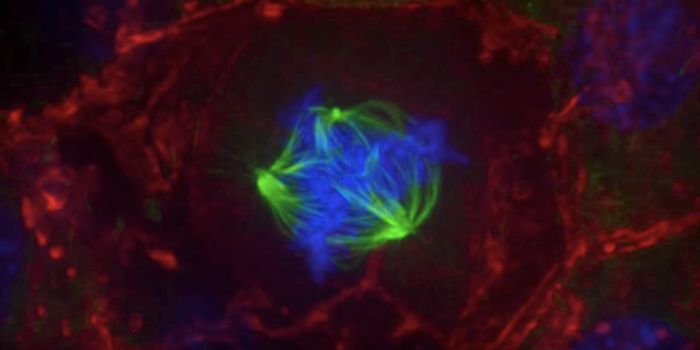

JUN 22, 2017Cell & Molecular BiologyResearchers have learned that our immune system plays an important role in stopping cells with an incorrect number of ch ...

MAY 21, 2019Cell & Molecular BiologyScientists have visualized how the body tests out important defensive cells, and have captured the process on video.